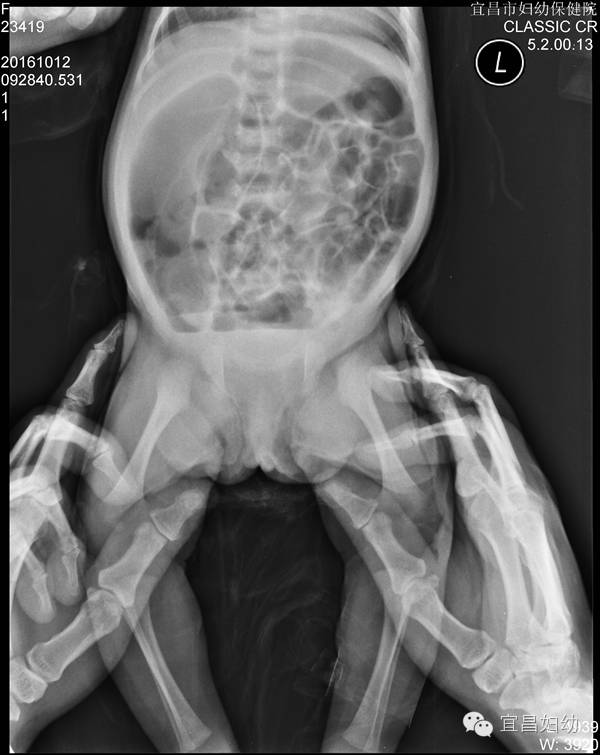

图一:动力性肠梗阻腹部平片。全腹部小肠结肠积气、扩张,结肠底部见液平面。